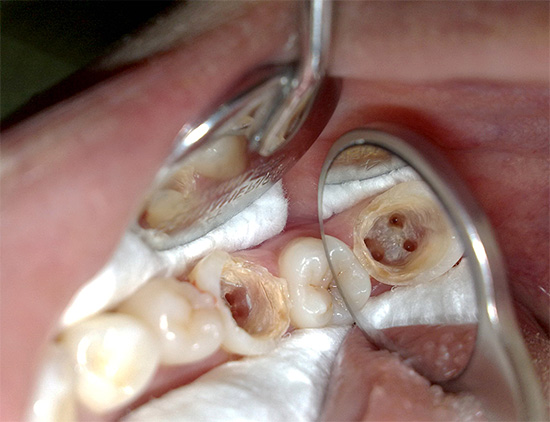

Se il mal di denti grave è associato alla parodontite ...

Con l'infiammazione alla radice, si sviluppa la parodontite. Allo stesso tempo, la polpa morta o i suoi resti si trovano nei canali del dente e il contenuto purulento del canale nella forma acuta della malattia si precipita verso le gengive, che provoca un forte dolore al dente, che non può nemmeno essere toccato.

La fornitura di cure di emergenza per la parodontite acuta è un compito importante per il dentista. Per fare questo, il medico apre il canale e lo lascia aperto per il pus, prescrivendo la soda e i risciacqui di sale. Una tecnica per il trattamento e il riempimento dei canali in una sola visita è possibile: per questo è importante creare una sterilità ideale nei canali, sigillarli in modo sicuro e, se indicato, prescrivere antibiotici.